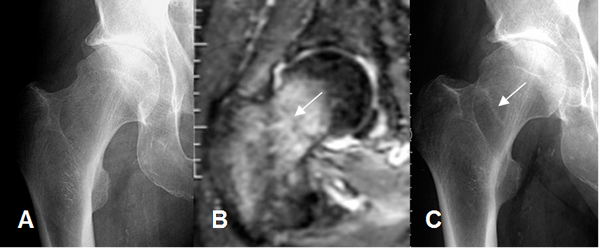

Fig 70 B. Fractura de stress.

A: Rx AP, donde no se detectan anormalidades.

B: RM coronal en STIR: Edema del cuello femoral, con fractura lineal a nivel transcervical.

C: Rx AP. Control luego de 1 mes, donde se aprecia imagen lineal y densa, que corresponde al callo óseo.